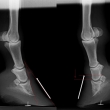

Sam - kladrubský hřebec s laminitídou a výhřezem kopytní škáry, teď krásně chodící a to hlavně díky velké pomoci podkováře, p.Schmidta